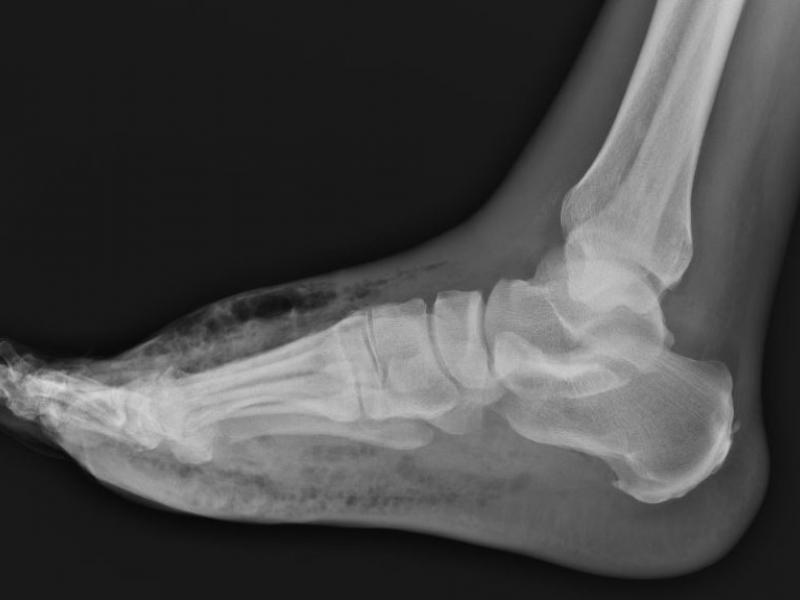

A 66 yo male hx of DM presents to the ED with right foot